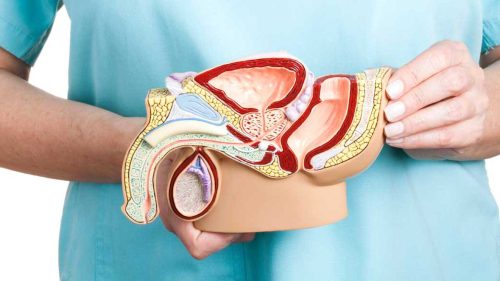

بهبودی پس از جراحی بزرگی پروستات

. بهبودی پس از جراحی بزرگی پروستات و انتظاراتی که از آن می توان داشت، چیست؟ اگر جزء میلیون ها مردی هستید که با هایپرپلازی خوش خیم پروستات (BPH) زندگی می کنند...

درمان های سنتی پروستات بزرگ شده

. هایپرپلازی خوش خیم پروستات یا پروستات بزرگ شده BPH، اگر بطور ناگهانی باید برای ادرار کردن به توالت بروید و یا در ادرار کردن مشکل دارید احتمالاً دچار بزرگی...